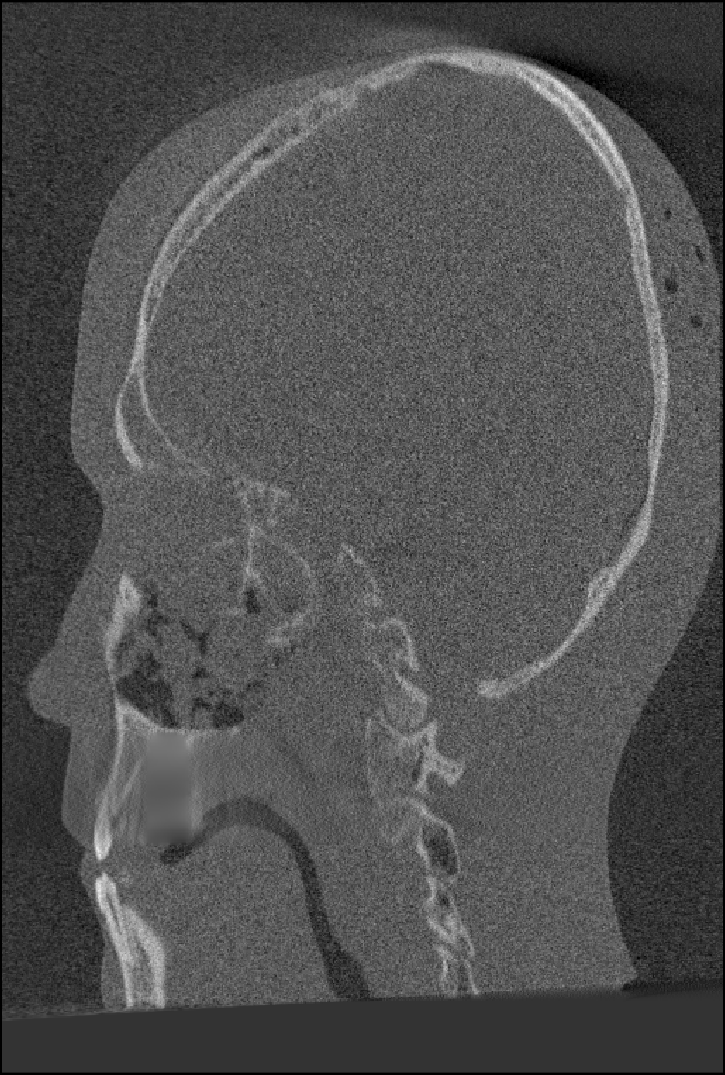

We computed the uncorrected FDK reconstruction, the image-domain hard-thresholding–based MAR reconstruction, and the proposed projection-domain complex wavelet MAR reconstruction for datasets (I–V). Fig. 4 shows selected slices from the reconstruction volumes for each dataset, displayed using identical windowing. The quantitative results of the metal segmentation are reported in Table 1 for datasets (I) and (II).

Dataset (V) presents a particularly challenging MAR scenario, in which the metal object is partially outside the reconstruction field of view (FOV). As a result, streaking artifacts are present even when the metal itself does not appear within the reconstructed volume. The large screw produces severe artifacts in the uncorrected FDK reconstruction. The image-domain HT-MAR approach is unable to reduce artifacts caused by metals outside the reconstruction FOV and additionally struggles with accurate boundary segmentation, especially in the coronal direction, where the screw geometry is particularly challenging. In contrast, the CW-MAR method is not affected by metals outside the reconstruction FOV, since segmentation is performed in the 3D sinogram domain, where the corresponding metal trace is present. Consequently, artifact reduction is effective. However, as in previous cases, projection inpainting introduces some blurring, which in this dataset leads to a loss of fine anatomical detail.